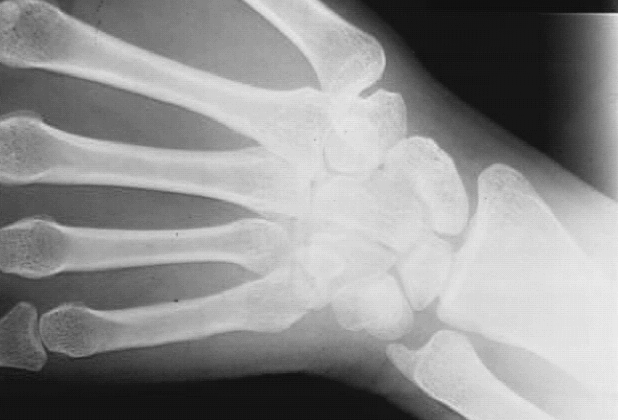

Upper Limbs:Wrist Bones: